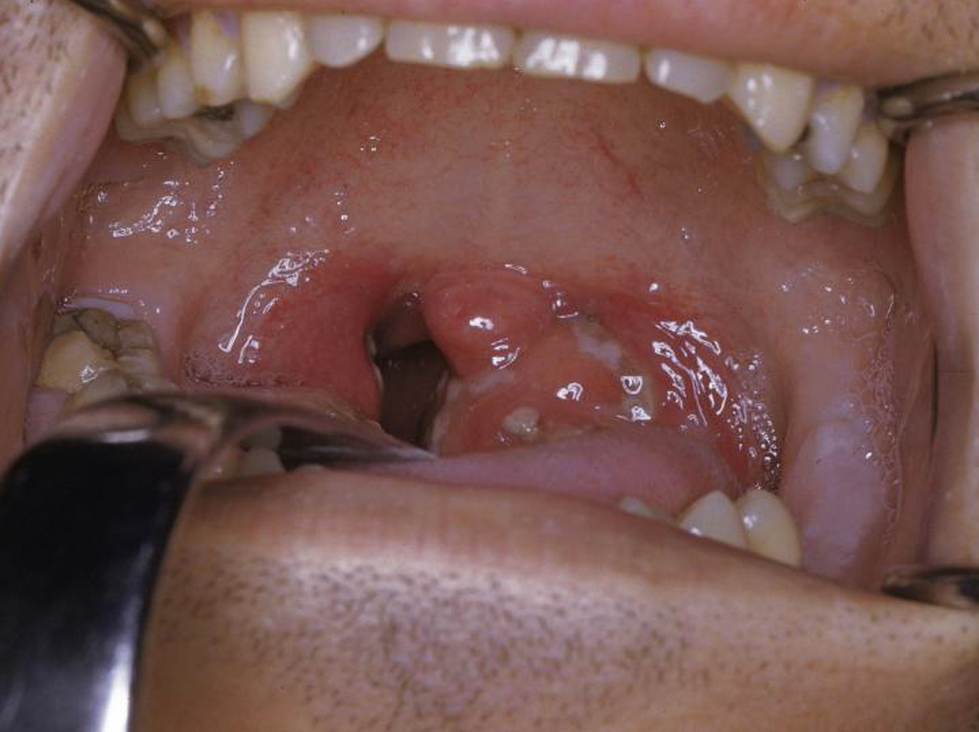

Các triệu chứng bao gồm khó chịu, sốt cao, nhức đầu, rối loạn tiêu hóa cũng như chứng hôi miệng và giọng nói bị nghẹt. Phát ban cũng có thể có thể xảy ra. Amidan sưng tấy, đỏ và thường xuyên có dịch mủ. Có thể có sưng đau hạch cổ. Sốt, nổi hạch, ban xuất huyết vòng họng và vỡ mủ thường là dấu hiệu phổ biến của viêm họng do liên cầu tan huyết β nhóm A (GABHS) hơn là với viêm amidan do virus, nhưng cũng có nhiều điểm trùng lặp. Với GABHS, có thể xuất hiện phát ban dạng scarlatiniform (ban đỏ).

Có thể dễ dàng nhận biết viêm họng dựa trên lâm sàng. Tuy nhiên, nguyên nhân của nó không dễ nhận biết. Sổ mũi và ho thường chỉ ra nguyên nhân do virus. Tăng bạch cầu đơn nhân nhiễm khuẩn (do virus Epstain Barr) được gợi ý khi nổi hạch vùng tam giác sau cổ, hội chứng gan lách to, mệt mỏi và khó chịu trong hơn 1 tuần, đốm xuất huyết trên khẩu cái mềm và dịch tiết amidan dày. Một lớp màng màu xám bẩn, dày và cứng, có thể chảy máu nếu bị bong ra trên bề mặt amidan cho thấy bệnh bạch hầu (hiếm gặp ở Mỹ).

- Amidan viêm có mủ;